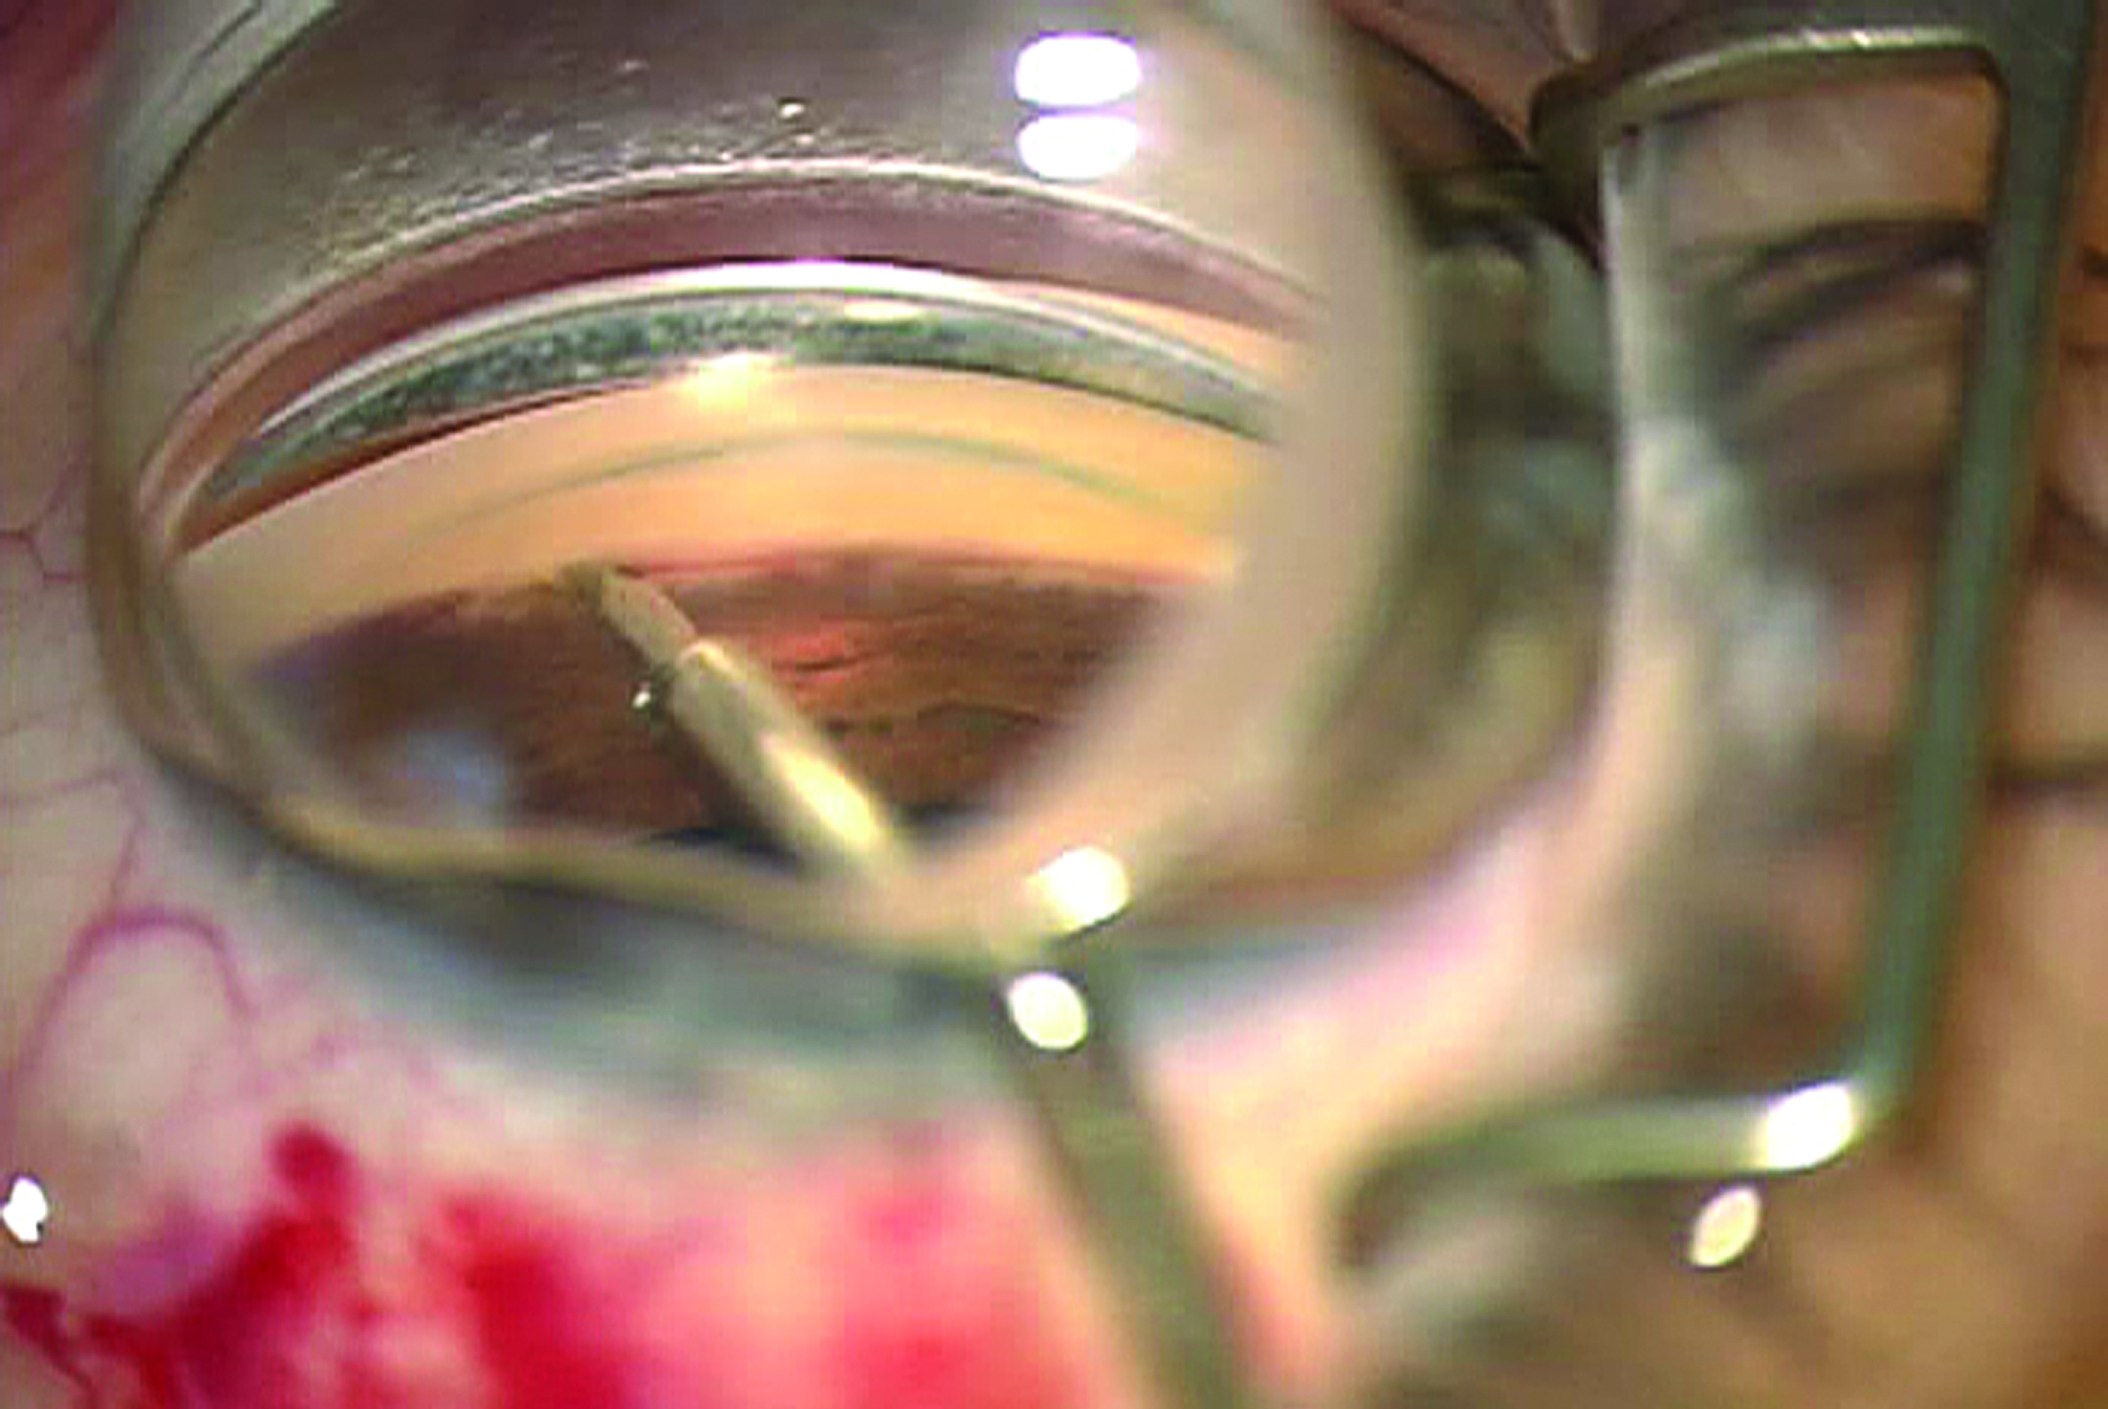

Trabectome cerrahisi gözden sıvı çıkışını artırır . Trabektomun ucu doğal drenaj yolunda akımı azaltan süzgeç benzeri dokunun(trabeküler ağ) kaldırılmasında kullanılır. Uygulama kornea dan yapılan küçük bir kesiden gerçekleştirilir.